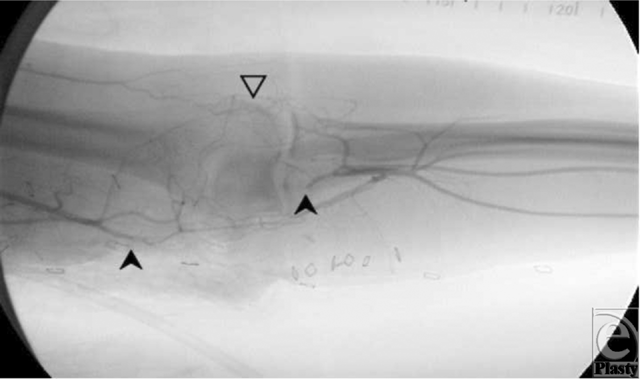

A 31-year-old man suffered an injury to his dominant left arm after falling through a skylight. Following initial resuscitation and operative hemostasis, the skin and muscle defect stretched from the level of the mid-humerus to the anteromedial elbow and measured 250 cm2 (Figure 1). Segmental loss of the brachial artery (8 cm) and the median nerve (7 cm) was also evident (Figure 2). An angiogram was obtained, which demonstrated adequate collateral circulation. Following continued exploration and debridement, a radial forearm flow-through free flap was raised from the ipsilateral side. The sural nerve was harvested, and 3 cabled nerve grafts were used to bridge the median nerve defect (Figure 3). The radial artery was interposed between the proximal and distal ends of the brachial artery, and the venae comitantes was anastomosed to the brachial vein. Vascular inflow to the hand was restored and the remainder of the flap was inset. The donor site was definitively closed with a split-thickness skin graft and Integra during the operation while a portion of the recipient site required a split-thickness skin graft (Figure 4). A negative pressure wound therapy (NPWT) device (EZ Care; Smith & Nephew, Largo, Fla) was used for dressing the donor and recipient sites.

Figure 2. Solid arrows: brachial artery. Open arrow: collateral vessels.